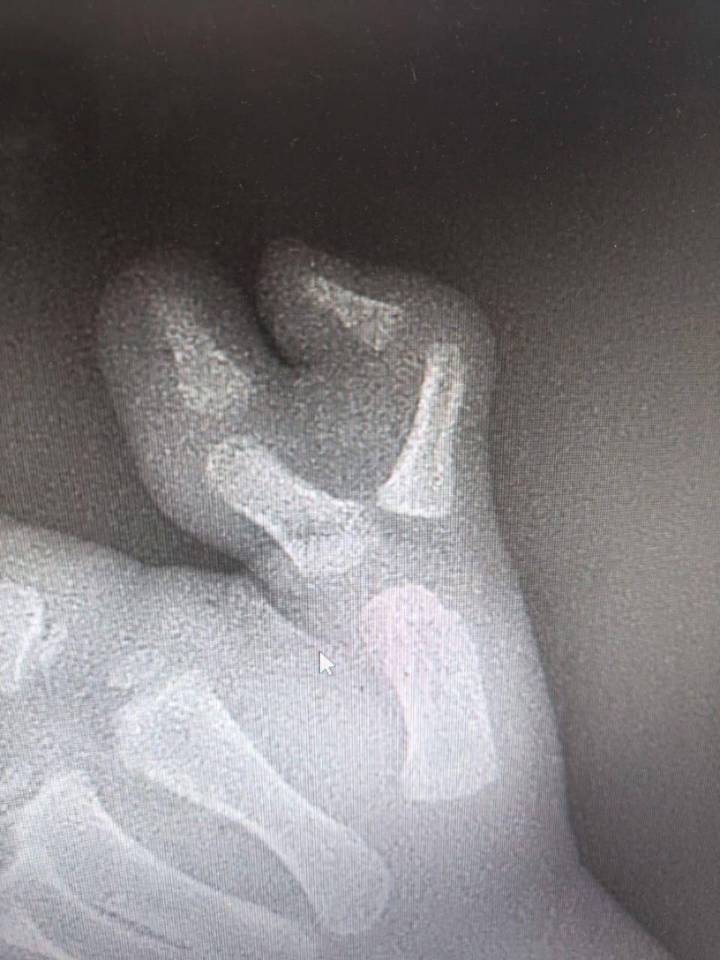

Врачи Московской областной детской клинической травматолого-ортопедической больницы (МОДКТОБ) удалили трехлетнему мальчику шестой палец на руке. Об этом в четверг, 27 ноября, сообщили в пресс-службе министерства здравоохранения региона.

— У маленького пациента рос добавочный палец, вызывая как физические, так и психологические трудности. После всех необходимых диагностических мероприятий ребенку провели операцию, — сказано в сообщении.

Как уточнили в пресс-службе, операция прошла успешно. На данный момент ребенка уже выписали из стационара на амбулаторное лечение по месту жительства. После полного восстановления мальчика ждет повторная операция для удаления металлоконструкции. Однако в дальнейшем функция кисти полностью восстановится, передает сайт Минздрава.

Подмосковные врачи удалили ребенку шестой палец на рукеПодмосковные врачи удалили ребенку шестой палец на руке / Фото: Пресс-служба министерства здравоохранения Московской области